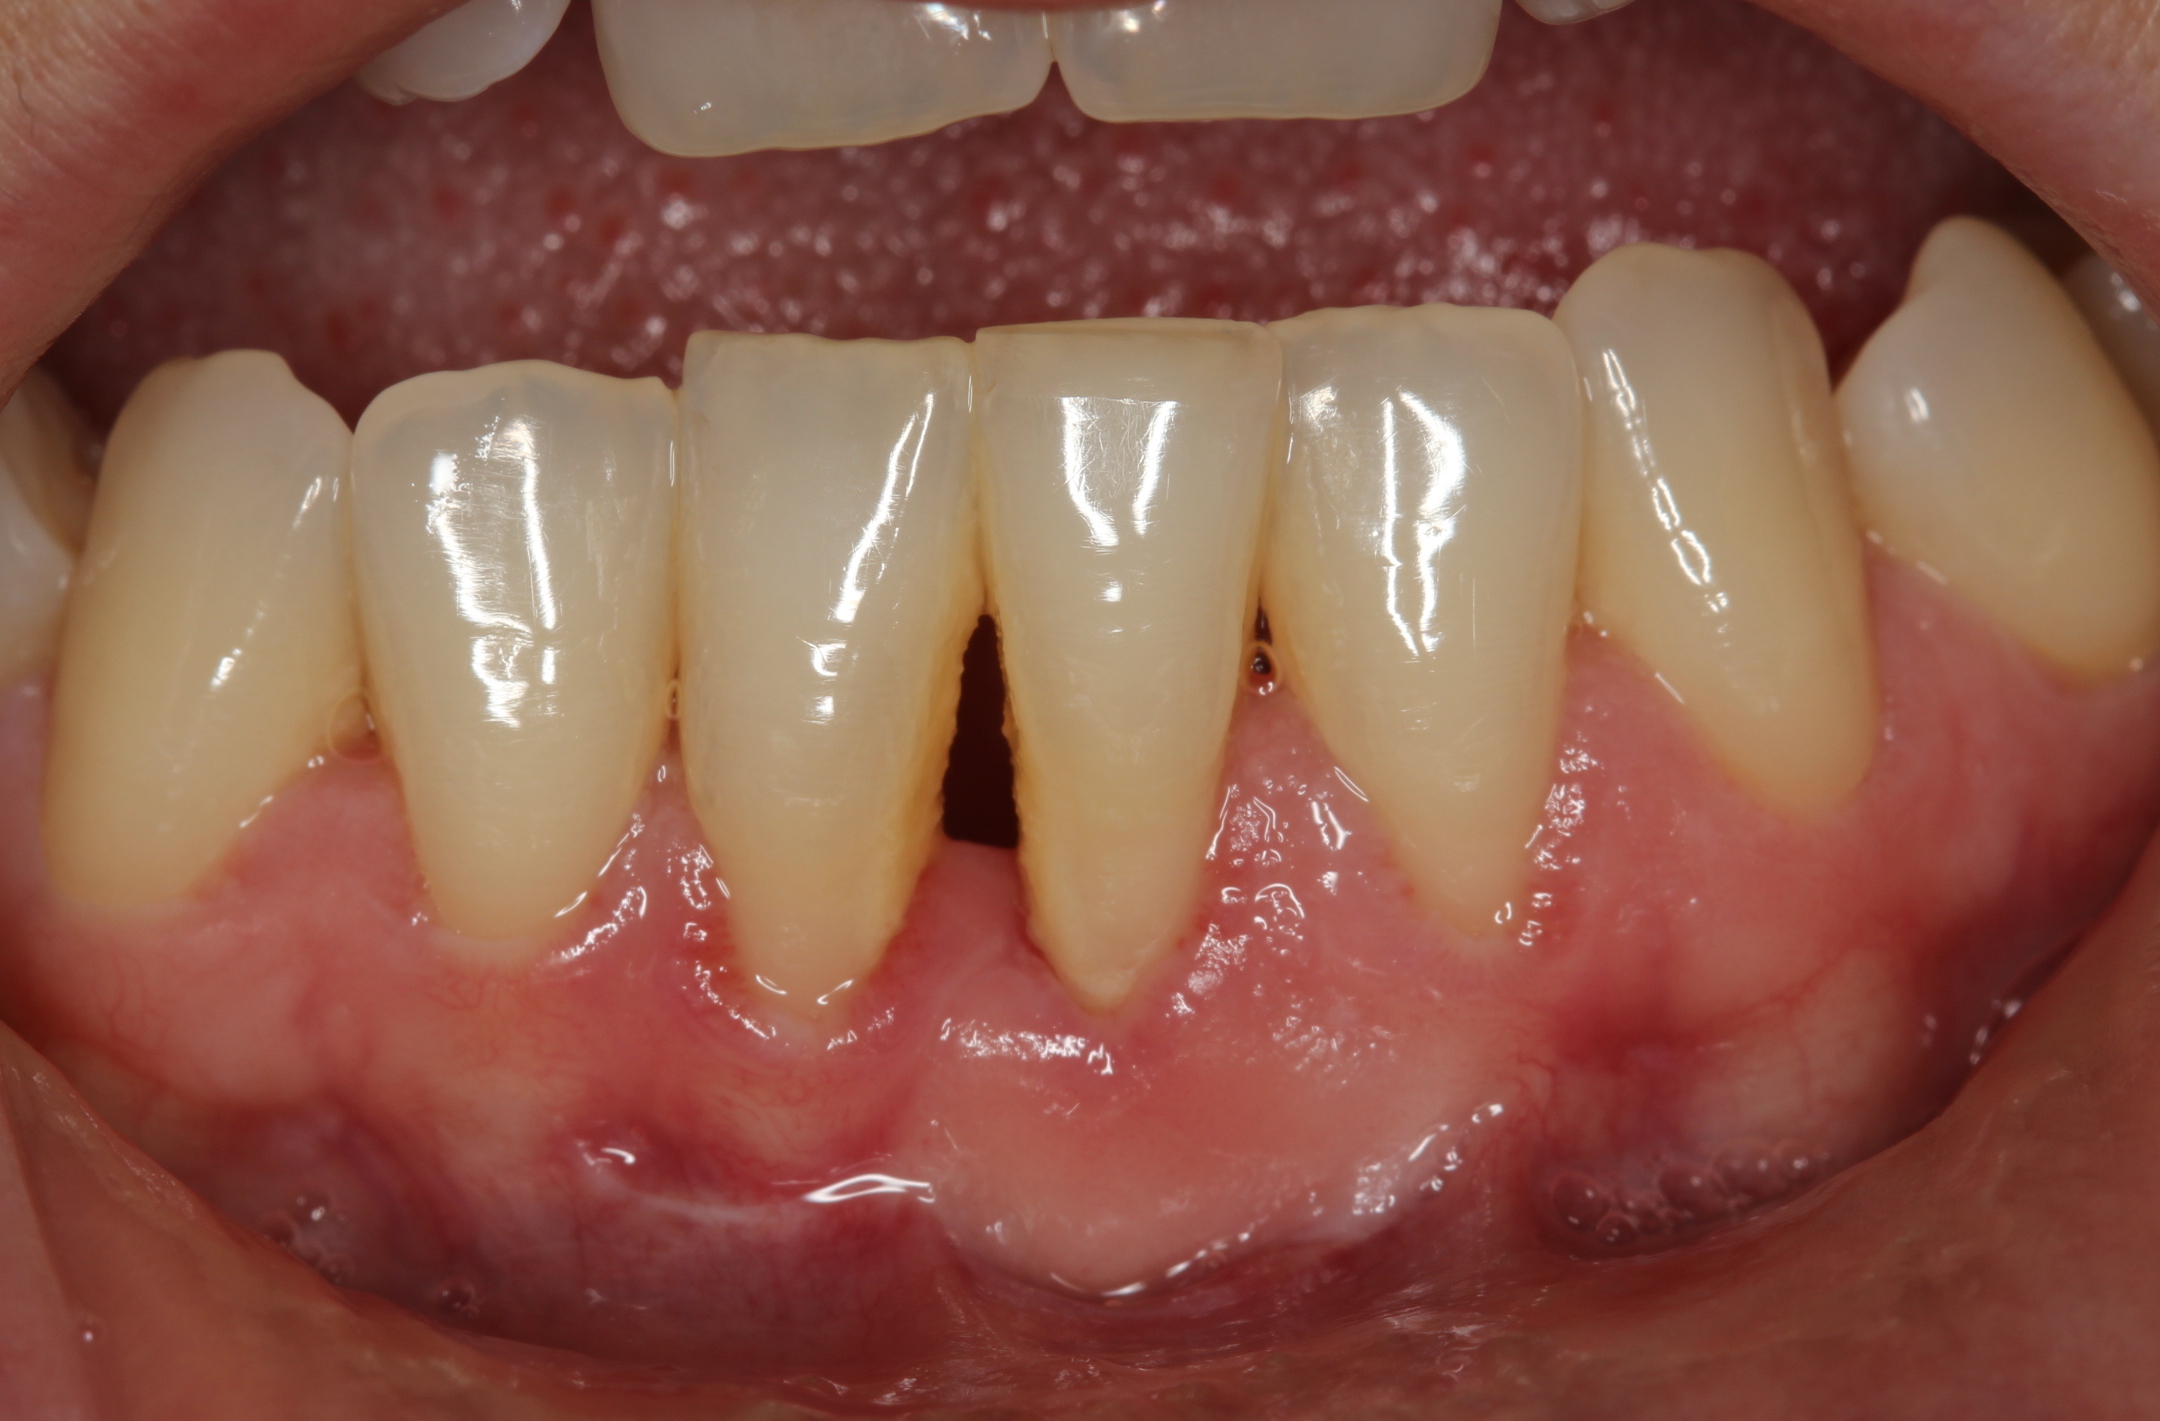

Methods: Four systemically healthy and non-smoker patients were referred to Abant İzzet Baysal University, Faculty of Dentistry, Department of Periodontology. Graft was harvested from palate and periodontal dressing wasn’t used. After surgery patient received LLLT using a 820nm diode laser, with output power of 1 W. immediately after surgery, on the first day, on the 7th day and lastly on the 14th day. Probing depth and FGG dimensions (horizonto-superior (HS), horizonto-inferior (HI), and vertical (V)) were assessed by using digital caliper at the same reference point and recorded before surgery, 1 and 3 months postoperatively.

Results: Although in this study we didn’t use periodontal dressing, healing was uneventful and patients' discomfort was minimum. Free gingival graft with assist of low level laser therapy show promising result for all following intervals. Graft dimensions were 10.00mm, 11.75mm and 6.25mm before the surgery; 8.5mm, 12.37mm and 5.87mm within the first month; 8.33mm, 9.66mm and 5.33mm within first three months for HS, HI and V; respectively. Normality of distribution was tested with the Shapiro–Wilk procedure. Kruskal-Wallis was used for the intergroup comparisons. There were no significant differences between the time interval.

Conclusions: The results showed that LLLT was an effective adjunctive treatment in promoting revascularization during early healing of FGG. In addition these results may support the idea of low-level laser therapy as a supportive therapy in patients receiving free gingival graft.